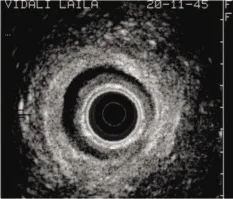

Le canal anal est étudié de haut en bas. Trois niveaux de coupe doivent être systématiquement repérés : coupe supérieure en regard du pubo-rectal (Fig. 1), coupe intermédiaire avec visualisation du SAI et du SAE (Fig. 2), et coupe inférieure avec présence exclusive du SAE.

Figure 1. Coupe au niveau du muscle pubo-rectal

Échoanatomie normale (Figs 1 et 2)

Nous décrirons l’aspect mis en évidence lors d’un examen réalisé avec une sonde rigide. L’interprétation des données anatomiques est complexe. Autour du cône apparaissent des couches concentriques hyperéchogènes et hypoéchogènes (Fig. 2).

Le muscle pubo-rectal (Fig. 1) est fondamental à repérer puisqu’il représente la limite supérieure du sphincter anal. Il forme un «U» ouvert en avant, discrètement hyperéchogène et hétérogène [9].